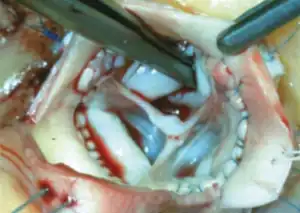

CT of the chest. Coronal (left) and axial (right) views demonstrating pathologic dilatation of the aortic root and ascending aorta. On the axial image, a dissection plane is noted in the aortic root. -

Degeneration of pulmonary autograft and aortic dissection extending into the non-coronary sinus.